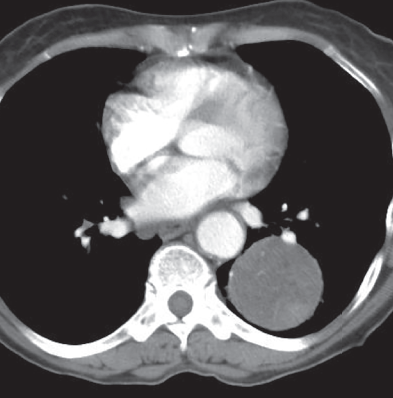

A 49-year-old male presented to the emergency room with hemoptysis, coughing up 400 cc of bright red blood.

A 71-year-old female with no significant past medical history presented to the hospital with sudden onset of massive hemoptysis.

A 46-year-old male presented with a history of intermittently increasing dyspnea on exertion over the past 3 years.